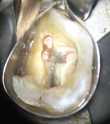

Conventional Treatment with Standard Core Restoration

Non-surgical endodontic treatment with resin core build up